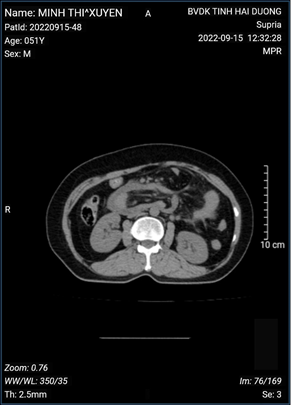

Phẫu thuật lấy sỏi ống mật chủ sử dụng laser tán sỏi đường mật trong ngoài gan bằng ống soi mềm trong mổ

Phẫu thuật điều trị sỏi đường mật sử dụng laser tan sỏi trong mổ đã được triển khai lần đầu tiên tại Bệnh viện Đa khoa Hải Dương. Để nâng cao chất lượng điều trị, giúp người bệnh có thể lấy tối đa sỏi đường mật, vị trí mà các dụng cụ lấy sỏi thông thường không thể lấy được, các bác sĩ khoa Ngoại tiêu hóa ổ bụng đã thực hiện phẫu thuật mở ống mật chủ lấy sỏi kết hợp sử dụng laser tán sỏi và ống soi mềm trong điều trị sỏi ống mật chủ, sỏi đường mật trong gan giúp kiểm soát hiệu quả đường mật trong ngoài gan, đảm bảo sạch sỏi triệt để, lưu thông mật ruột tốt, không phải đặt dẫn lưu đường mật kéo